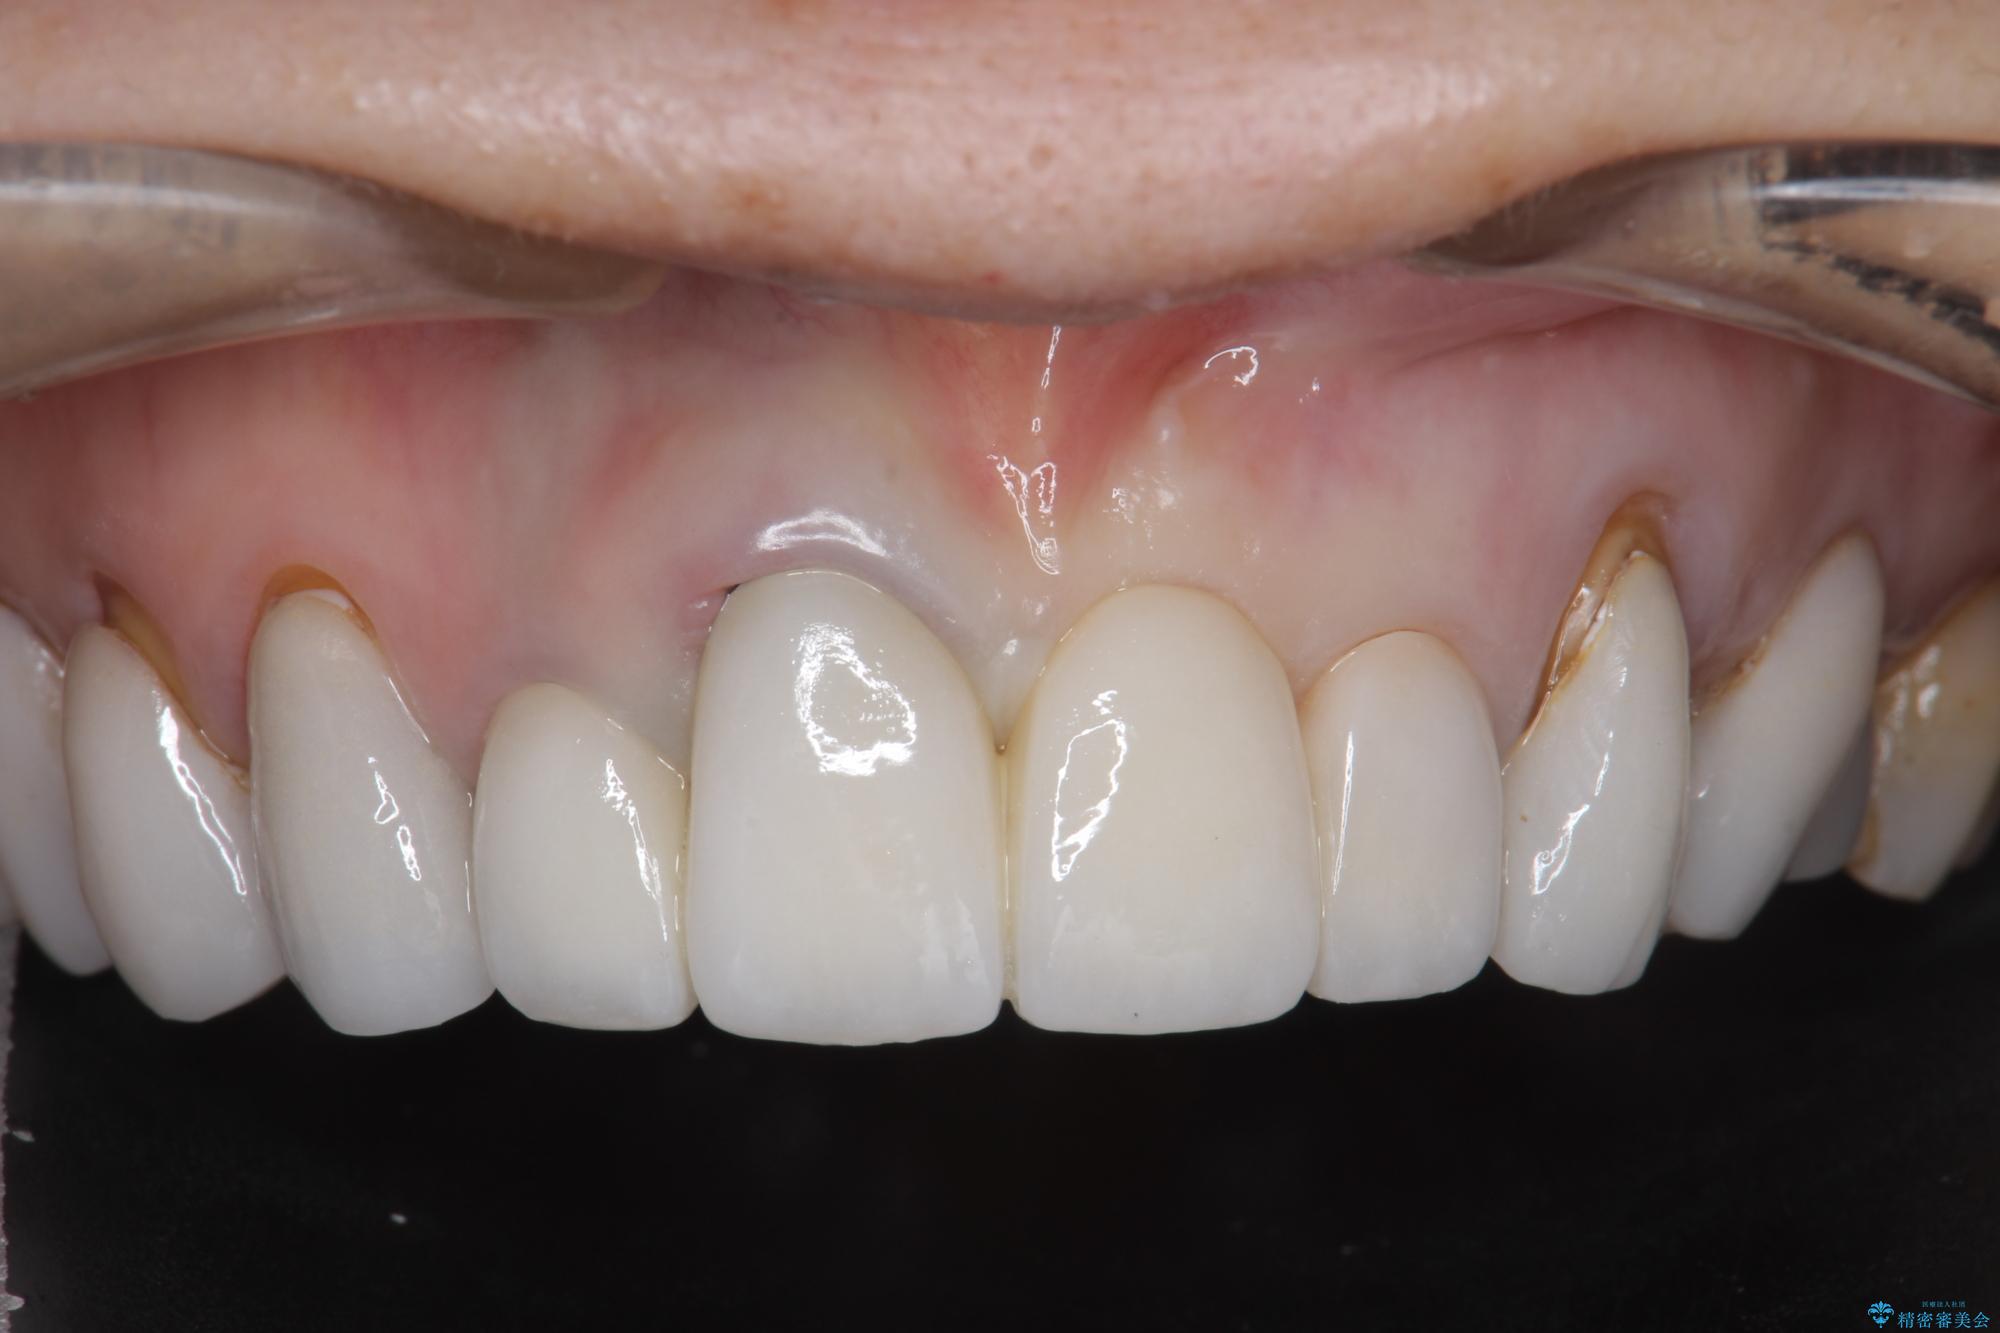

[ セラミック治療 ] 歯ぐきの際の黒ずみを改善したい

- 歯ぐきとセラミックの間の黒ずみが目立つので、きれいに治してほしい。と希望され来院されました。

歯ぐきの位置が変化しクラウン下の歯が見えるようになってしまったことで、審美障害が生じている状態です。

クラウンマージンの再設定を行うことで、黒ずんだ部分を再度覆い、審美障害を改善します。

- 52.8万円(ジルコニアクラウン×4・仮歯×4)費用は治療当時の料金となります